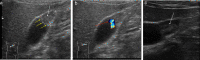

Gallbladder polyps are protuberances of the gallbladder wall projecting into the lumen. They are usually incidentally found during abdominal sonography or diagnosed on histopathology of a surgery specimen, with an estimated prevalence of up to 9.5% of patients. Gallbladder polyps are not mobile and do not demonstrate posterior acoustic shadowing; they may be sessile or pedunculated. Gallbladder polyps may be divided into pseudopolyps and true polyps. Pseudopolyps are benign and include cholesterolosis, cholesterinic polyps, inflammatory polyps, and localised adenomyomatosis. True gallbladder polyps can be benign or malignant. Benign polyps are most commonly adenomas, while malignant polyps are adenocarcinomas and metastases. There are also rare types of benign and malignant true gallbladder polyps, including mesenchymal tumours and lymphomas. Ultrasound is the first-choice imaging method for the diagnosis of gallbladder polyps, representing an indispensable tool for ensuring appropriate management. It enables limitation of secondary level investigations and avoidance of unnecessary cholecystectomies.